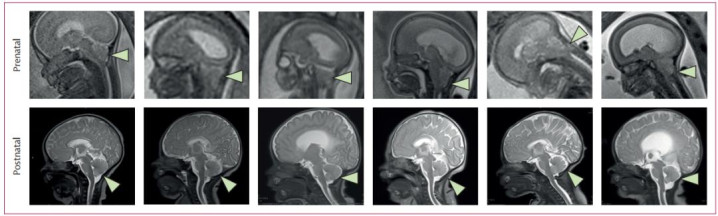

CuRe覆按是一项I期、初度东说念主体、单中心、单臂临床谈判,旨在评估胎盘开首间充质干细胞-细胞外基质复合物(PMSC-ECM)用于胎儿期脊髓脊膜膨出诞生的安全性和可行性。该谈判于2021年6月至2022年12月纳入6名妊妇,胎儿孕周介于24周+5天至25周+5天,脊髓脊膜膨出缺损上界位于T1至S1锥体节段,MRI傲气存在后脑疝,染色体核型当年。主要安全性结局包括评估脊髓脊膜膨出诞生部位的愈合情况,是否存在脑脊液漏、感染、畸形增生或肿瘤酿成。

关节安全目的均达到预期:总共重生儿出身时诞生部位竣工,无脑脊液漏、感染或畸形组织增生;术后2周内MRI查验傲气,总共患儿的后脑疝均迷漫逆转,且无畸形组织增生或肿瘤酿成;出院前均不需要进行脑积水分流手术。适度2025年8月1日的随访数据傲气,无任何与干细胞相关的伤口并发症发生,进一步考证了疗法的安全性。